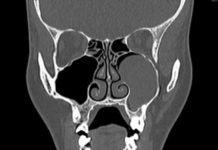

КТ околоносовых пазух: что показывает и где сделать процедуру

Компьютерная томография (или КТ) околоносовых пазух - это процедура, используемая для диагностики придаточных пазух носа. Она представляет собой процесс послойного получения снимков тела человека....